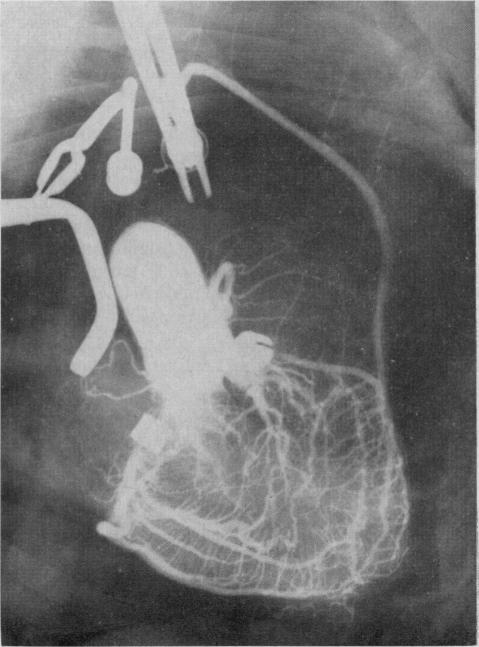

Atherosclerosis obstructs the main stems of coronary arteries, restricting the coronary artery inflow tract. Nature develops intramyocardial collaterals but fails to form extracoronary collateral channels. It is only through surgical measures that extracoronary collateral channels may be formed, for example, by internal mammary artery implantation and omental graft without pedicle operations. Preoperative assessment, with particular reference to anginal pain, disease activity, indications for and contra-indications to surgery, is outlined. The importance of cine coronary arteriography is stressed. The results of internal mammary artery implantation with or without omental graft in patients followed up for two to 14 years are presented. Operative mortality in 103 consecutive patients was 2.9%. There was marked improvement in over 70% of 115 patients reviewed. Post-operative examination of 29 implanted internal mammary arteries showed that 76% were open when examined up to 10 years postoperatively; many of these were studied by cineangiography.